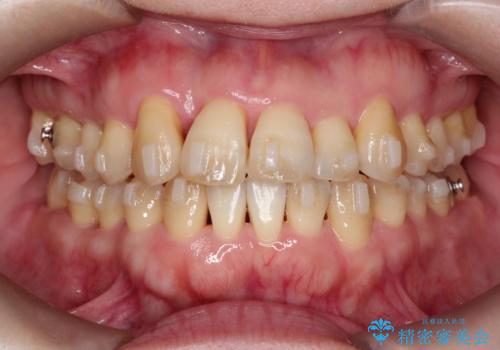

【インビザライン】ずれた前歯の噛み合わせをなおしたい

- 前歯の噛み合わせが悪いことを主訴に来院されました。

歯周病も併発していたため、歯牙への負担が少なくなるように治療計画をたて、インビザラインにて治療を完了しました。

矯正開始前に半年間、歯周治療を行ってからインビザラインを装着しています。